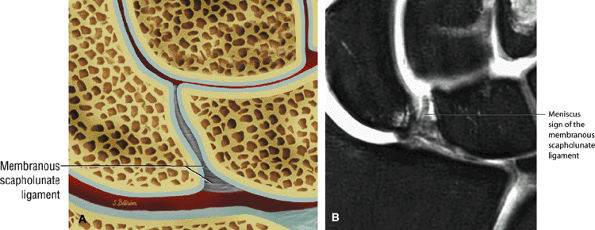

FIGURE 10.74 ● Membranous wedge-shaped component of the scapholunate ligament with direct proximal attachment to the articular surfaces of the scaphoid and lunate. The distal apex is free without direct attachment and presents as a prominent distal protrusion into the scapholunate articulation. (A) Coronal color illustration. (B) Coronal FS PD FSE image.